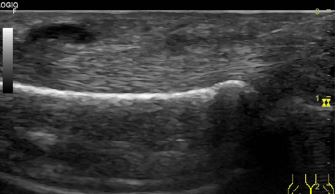

Hallazgos ecográficos

Se visualiza engrosamiento hipoecoico difuso en polea A1, líquido en las inmediaciones del tendón y tendón tumefacto.